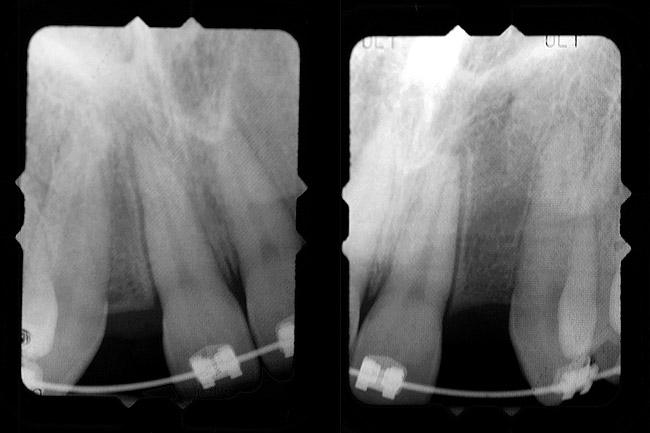

Periapical radiographs were taken to help determine the mesial-distal inclinations of the adjacent tooth roots (Figure 1). The radiographs revealed a serious issue, convergent roots for the right canine and right central, which eliminated that area as a potential implant-receptor site. The space between the left central and canine teeth was minimal, although the roots were relatively parallel. Clinical examination (manual palpation of the root eminences superiorly to the vestibule on the right side) confirmed the root convergence (Figure 2A). The flat, wide zone of the keratinized tissue and lack of interdental papilla was evident for the missing right lateral incisor. There was a marked difference in clinical appearance for the left lateral, which could impact the eventual plan of treatment (Figure 2B). Other significant clinical findings included bilateral facial bone concavities, which existed as a result of the congenitally missing tooth roots. As a diagnostic cue to the underlying bone topography, it is important to follow the demarcation between attached and unattached gingival tissue, and note the crestal width of the available keratinized tissue (Figure 2C).

Based upon the intraoral examination and periapical radiographs, additional orthodontic intervention was r.commended to move and rotate the roots to gain enough space for implant placement. This information was conveyed to both the parents and to the treating orthodontist. After several additional months, a panoramic radiograph was provided by the orthodontist to evaluate the distance between the clinical crowns and tooth roots (Figure 3). The lack of sharpness, definition, and radiographic artifacts made it impossible to determine whether implants could be successfully placed based on the 2D panoramic image. This diagnostic predicament was discussed with the patient and his parents, and it was suggested that a CT scan would be necessary to accurately assess the bone topography and spatial orientation of the adjacent roots. The parents agreed, and the patient was given a prescription for a CT scan study at a local radiology center.

Figure 1  Pretreatment radiographs revealed convergent roots for the right canine and right central.

Figure 1

Figure 3  After orthodontic therapy, the radiograph did not provide enough diagnostic information to determine if implants could be placed.

Figure 3